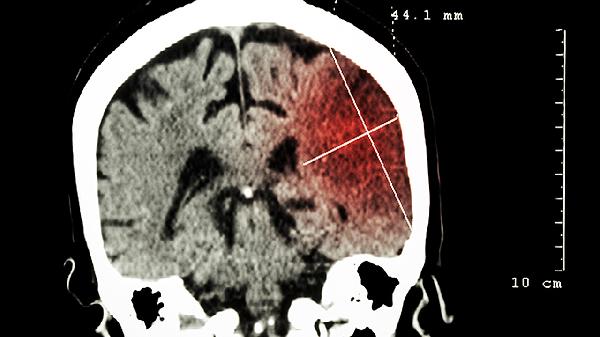

服用期间忌食辛辣刺激性食物,避免情绪激动。需在医生指导下根据病情调整用药周期,定期复查头部影像学检查。肢体功能障碍者应同步进行康复锻炼,言语不清患者可进行发音训练。出现皮疹、恶心等不良反应时应及时停药就医。